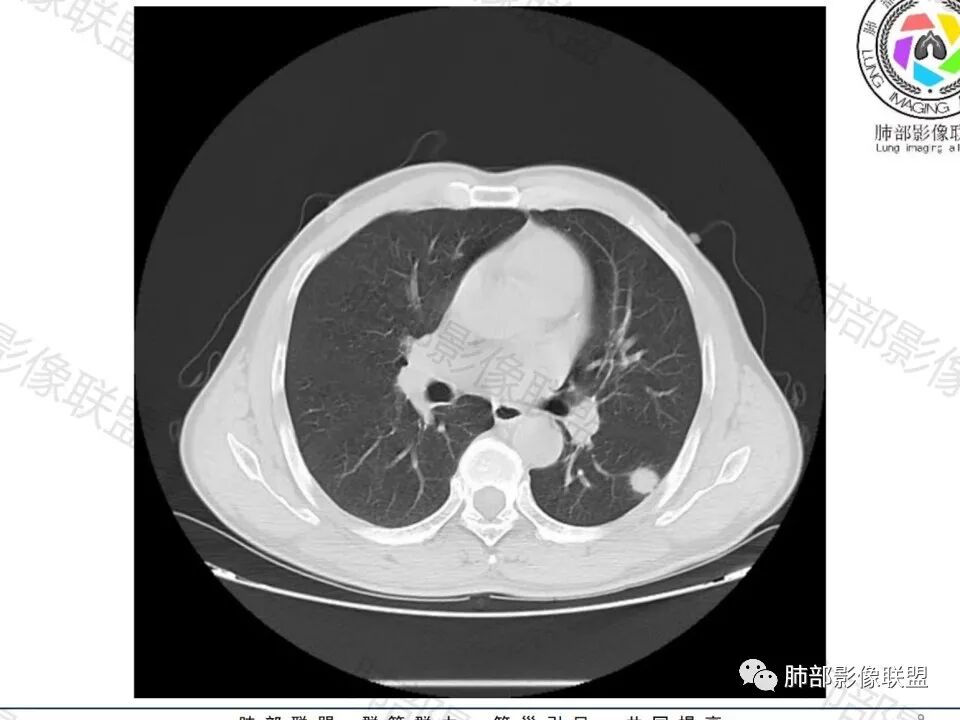

病史:男,60岁,体检左下肺结节,肿标阴性;

影像:轻微肺气肿,可能抽烟;旁边有个卫星灶4-5个,厚层无血管弯,薄层叶间裂轻度增厚,有囊腔,内侧有一个微血管,弯,另有两个微血管直,膨隆,增强血管不弯,糊墙,好像边界有些模糊,17-47-47,冠位轻度叶间裂弯。

诊断:警惕良性,隐球菌感染?

鉴别:腺癌,无磨玻璃,模糊?糊墙;纵膈窗太光滑,胸膜面广;不膨隆。支持点,薄层毛刺,强化。

老年男性,无症状,肺气肿背景

这个囊可靠吗?

这应该是附近的肺气肿

血管进去还是比较自然

南边:

类圆形,边缘稍平直,周围晕中细微毛刺,密度均匀,均匀强化,血管走形自然,稍牵拉扭曲,支气管在近端堵塞

多发类似结节

常规思路:

1、炎性结节,多发,类似,晕,隐球菌?

2、恶性:多发:转移瘤?肺癌并多发转移瘤?

大家目前碰到多数结节是磨玻璃结节,对于实性结节的诊断反而陌生,其实性结节才是考验脑子的时候;

这枚结节的纵隔窗在没有调节窗位的情况下,已经很密实了,说明这个结节里面是软组织的成分,这与普通炎性结节(隐球菌等)的密度还是有区别的,很多年前就有人提出,纵隔窗显示越大,恶性可能越大;

结节周围有磨玻璃影,边界似清不清的,但是总体不如炎性晕征那么模糊;

增强的程度很难讲,但是不均匀强化是可以确定的;

有收缩力,但是很轻,按照常理,实性结节因为有占位效应,不太会有收缩力,但是叶间胸膜有凹陷。所以讲,这个结节还是开了放心。